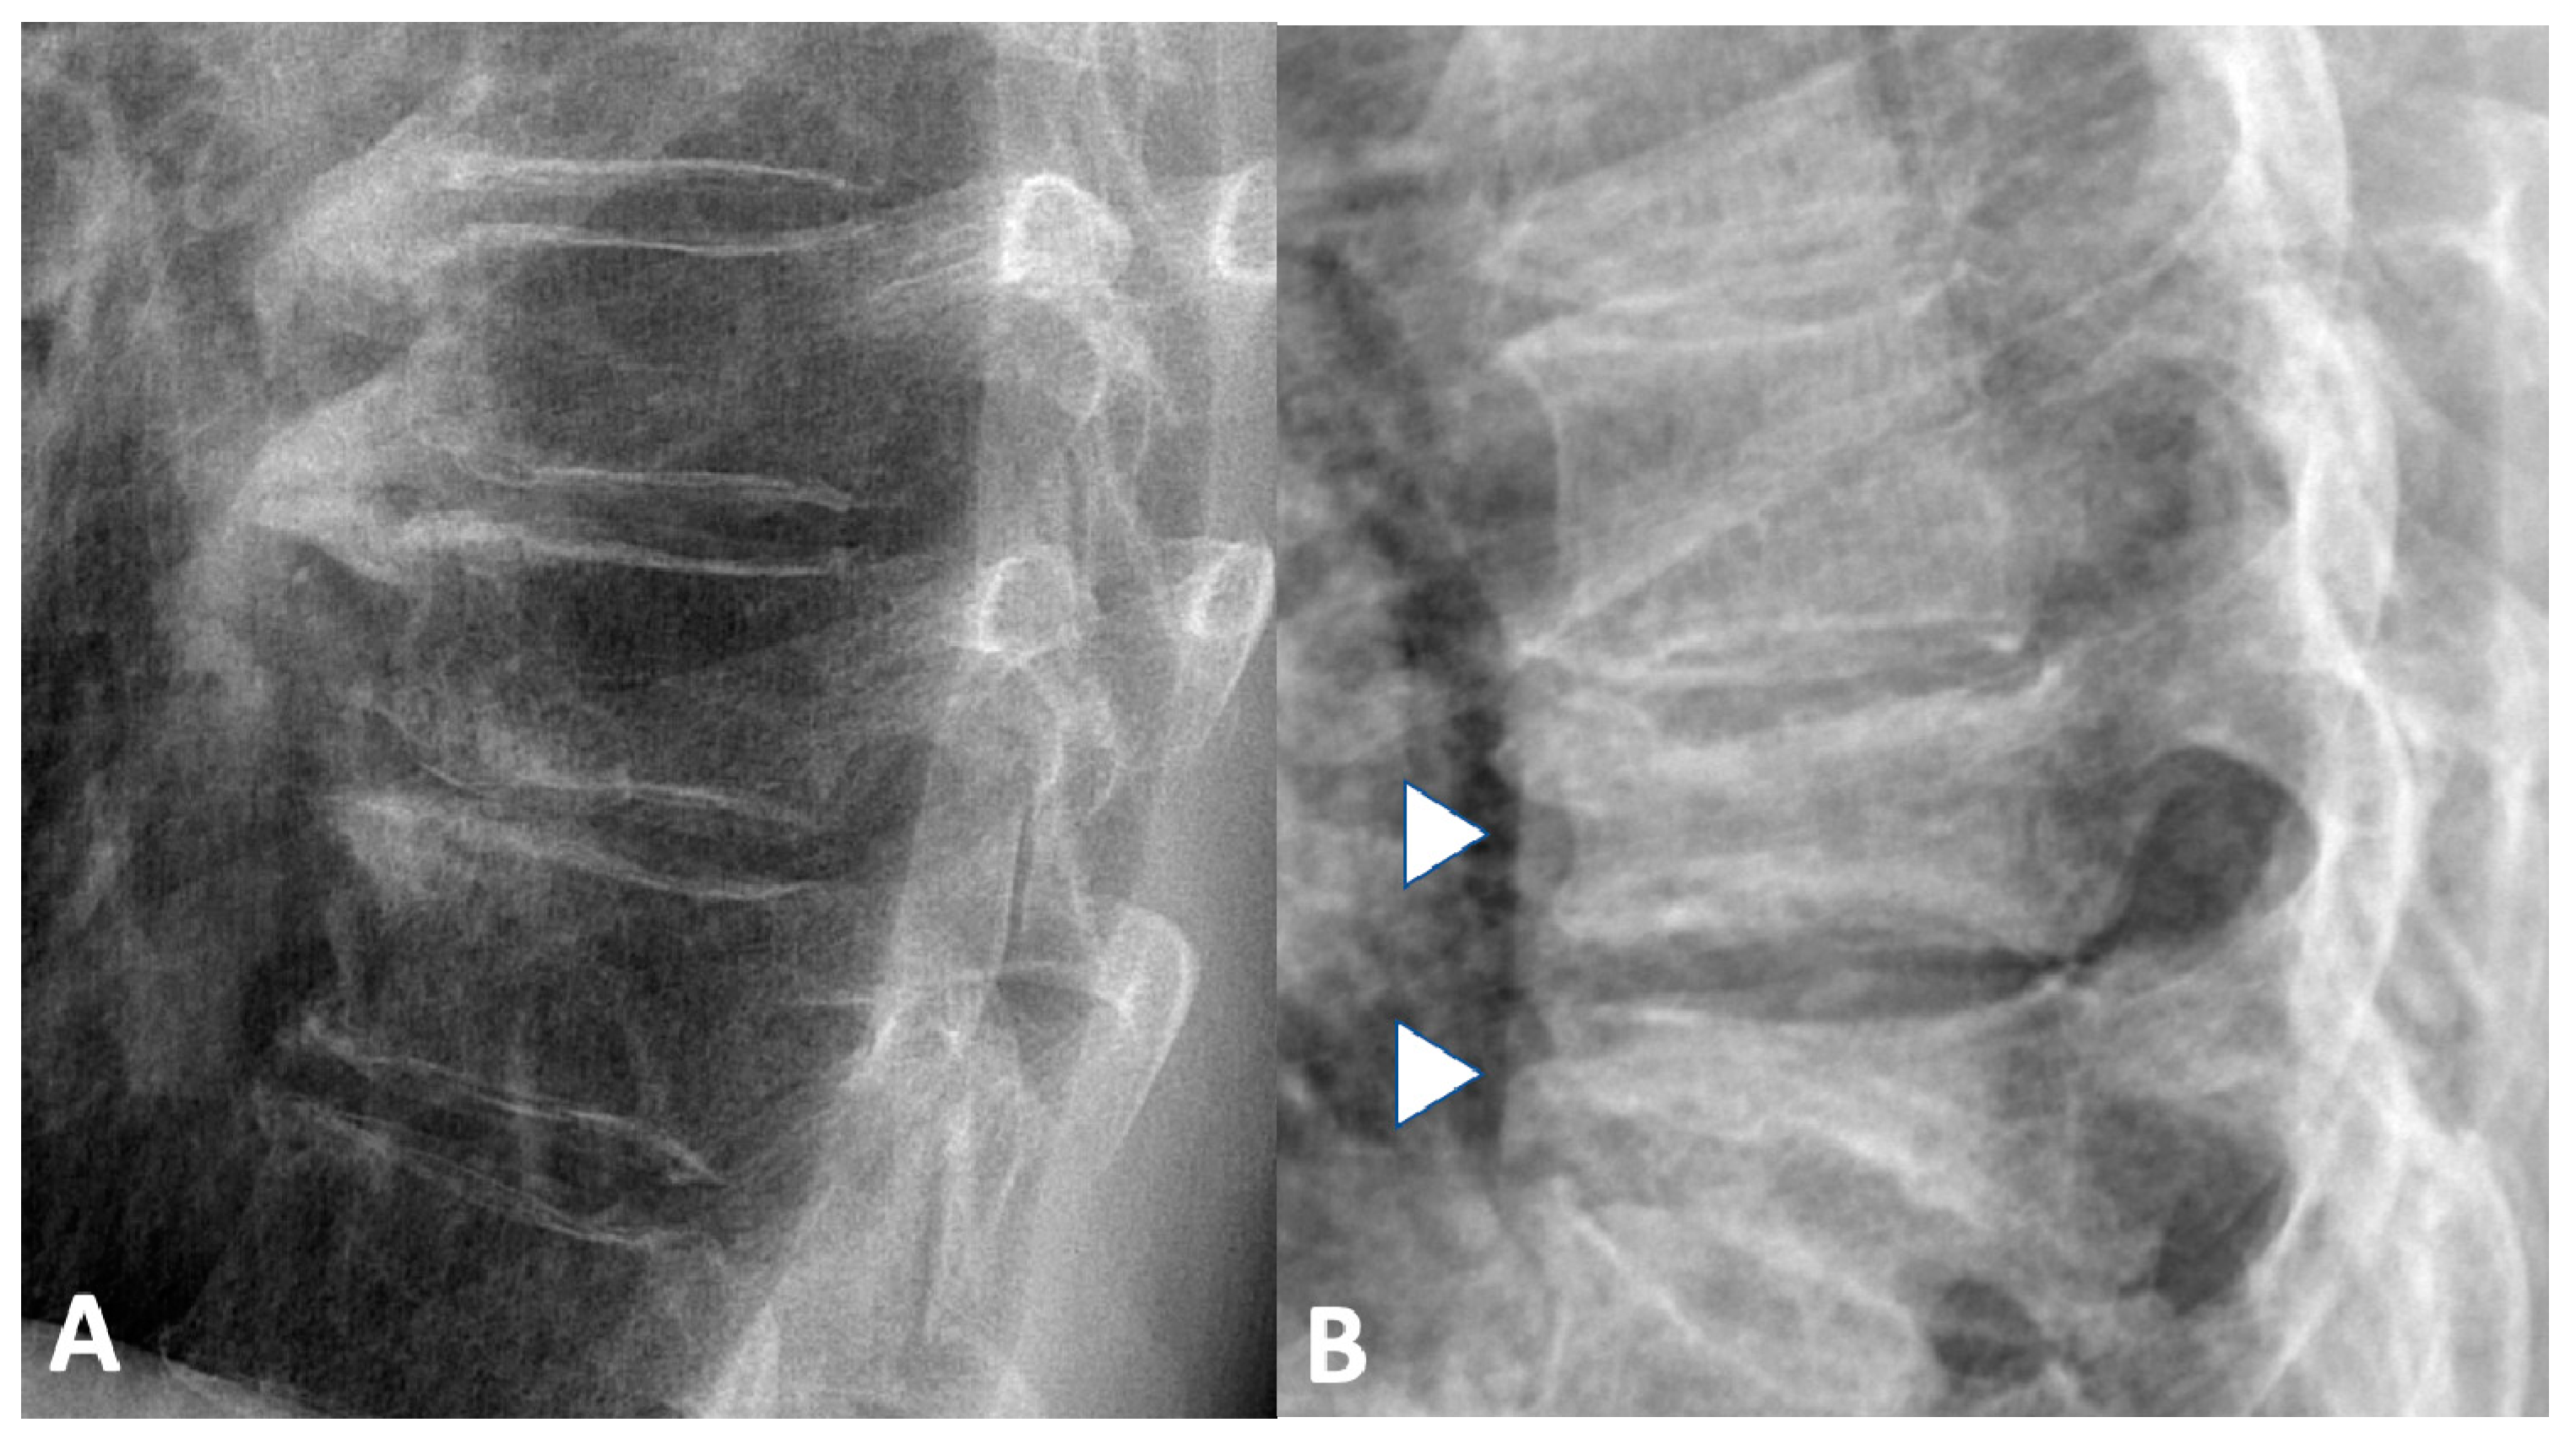

2.1.2. Spine

3. Imaging in the Assessment of Non-Inflammatory Musculoskeletal Manifestation